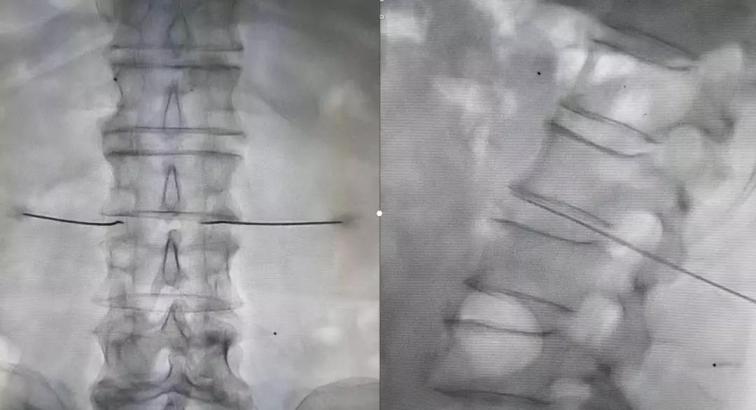

隨后制定了詳細(xì)的診療方案:1、進(jìn)一步完善相關(guān)檢查;2、每天早上給予骶管封閉、三氧血治療;3、實(shí)施腰交感神經(jīng)阻滯改善下肢血液循環(huán);4、待患者對(duì)初步治療效果認(rèn)可滿意后,給予腰交感神經(jīng)損毀治療,以此改善下肢血管痙攣性疼痛以及下肢血液供給狀況,給予保肢,達(dá)到治愈的目的。

診療方案雖然有了,但是要?jiǎng)褡杷伟⒁毯图覍佟敖刂钡哪铑^還真是頗費(fèi)周折。李巍安慰家人,按照醫(yī)生的方法治療3天,如果效果不好,我們?cè)偕塘拷刂氖虑?。家人半信半疑的答?yīng)了。8月20日,經(jīng)過(guò)幾天的初步治療,宋阿姨和家人們明顯感覺(jué)到了患病小腿上的好轉(zhuǎn)變化。李巍又詳細(xì)向患者及家屬解釋了交感神經(jīng)阻滯及損毀能夠給疾病帶來(lái)的相關(guān)改善,并在征求病人及家屬同意后,給予患者腰交感神經(jīng)損毀治療。實(shí)施治療的第二天,宋阿姨下肢血管神經(jīng)性疼痛癥狀明顯緩解,下肢供血明顯改善,左下肢皮膚溫度較術(shù)前明顯提升,結(jié)痂周圍皮膚顏色也變得紅潤(rùn)。